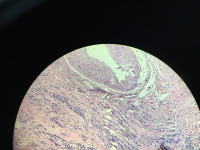

左乳肿物

性别

女

年龄

52

临床诊断

癌

一般病史

发现肿物1月

标本名称

大体所见

灰白结节直径2厘米